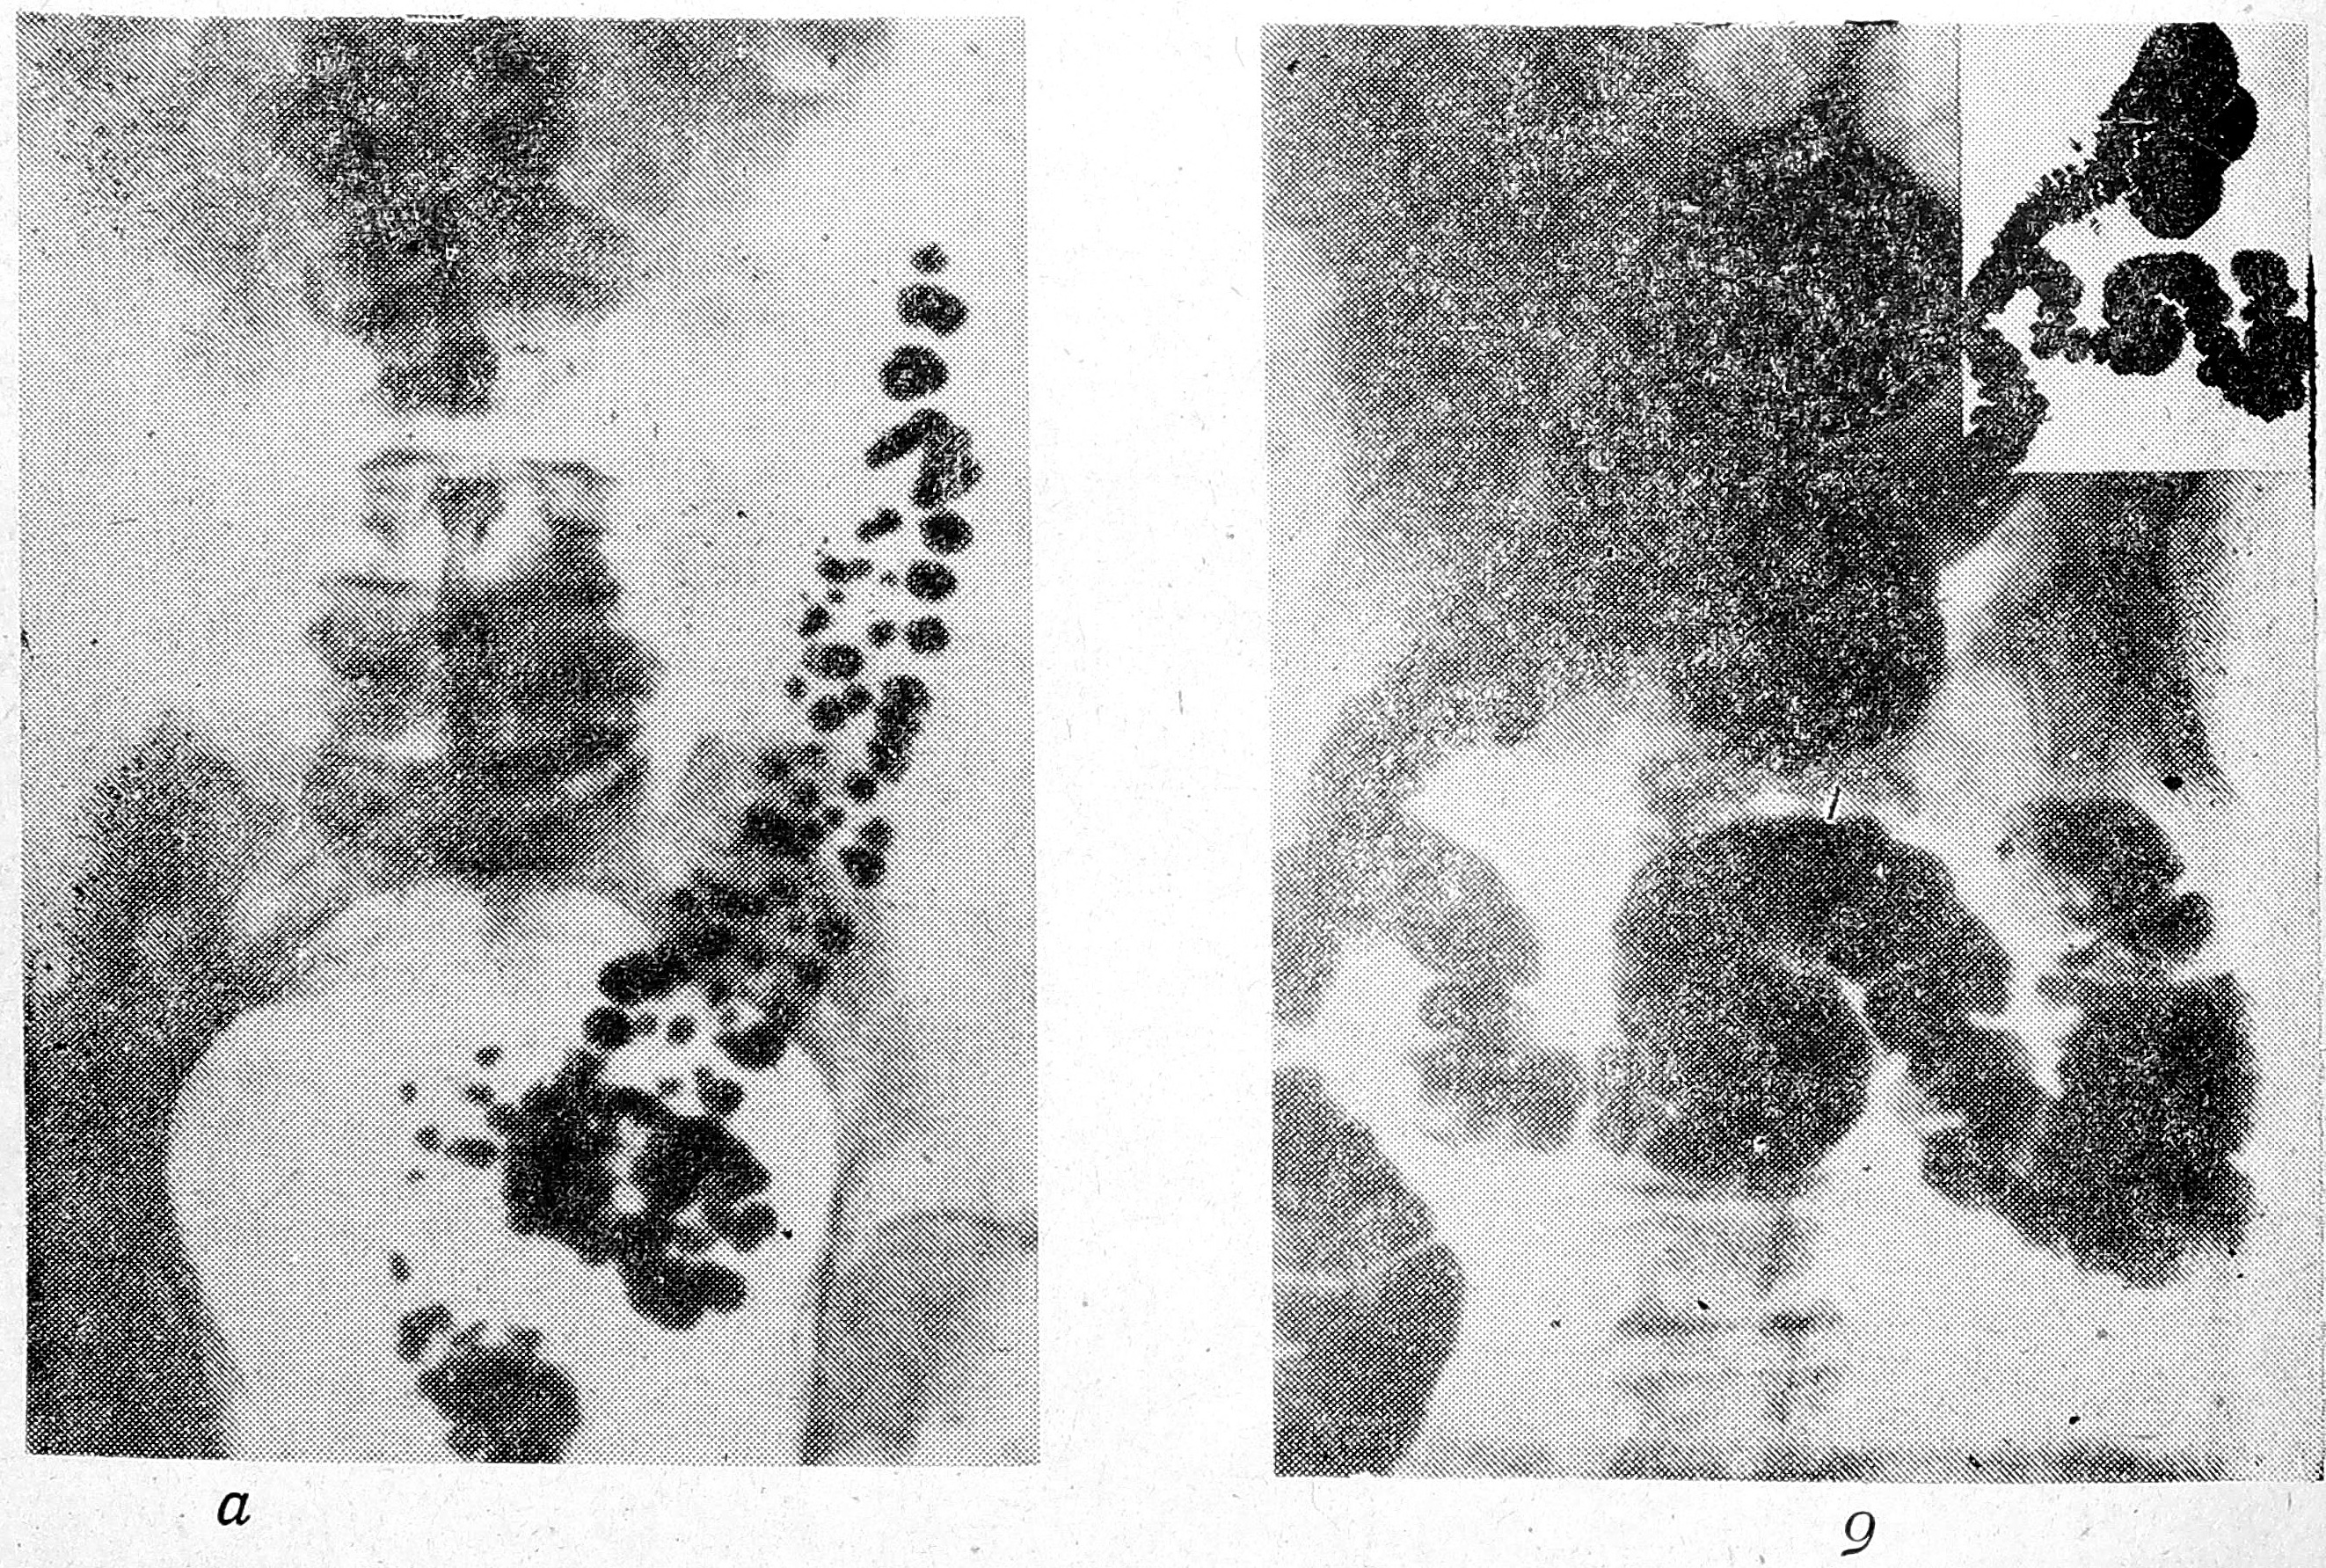

Для иллюстрации приводим снимки больной Г., 75 лет, направленной на рентгенологическое обследование с диагнозом колита. На снимке с тугим заполнением толстой кишки (рис. 1а) определяется неравномерность и зазубренность гаустрации в зоне сигмы. Отсроченная рентгенография через 48 ч после контрастной клизмы (рис. 16) выявила большое количество дивертикулов сигмы и нисходящей кишки. Применение спазмолитических препаратов (метацина, бускопана, но-шпы, папаверина) также способствует обнаружению дивертикулов. Указанные методические приемы эффективны при второй форме ДБТК, протекающей с явлениями усиленной мышечной сегментации.

Рис. 1. Б-ная Г., 75 лет. Исследование методом контрастной клизмы. а — тугое заполнение толстой кишки. Зона неравномерной гаустрации, б — снимок через 48 ч после контрастной клизмы. Задержка бария в полостях дивертикулов.